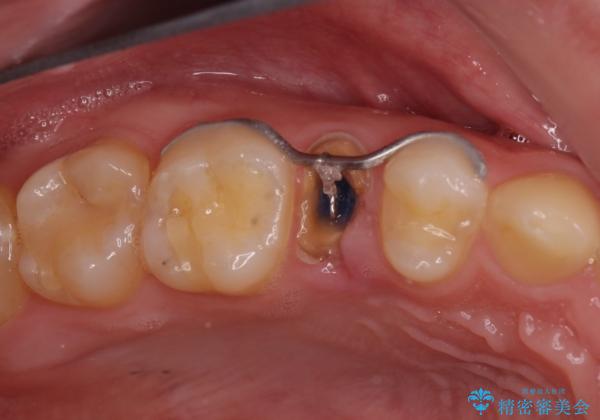

右上の被せものを除去したところ、中で歯が割れていたため、部分矯正で引っ張り出すことになりました。

歯を引っ張り出したり、歯肉の手術の経過待ちの間に、患者様のご希望で他の歯の虫歯治療も行いました。

・基本的には失活歯(根管治療済の歯)が対象となります。

・約3か月ほど引っ張り出します。

・両どなりの歯に一時的にワイヤーを接着します。

・十分に引っ張り出した後、歯肉の手術が必要となります。

・歯肉が落ち着いてから最終的な被せものの製作となります(約3か月)。

・歯の割れ方によっては引っ張り出す対象外となります(抜歯になります)。